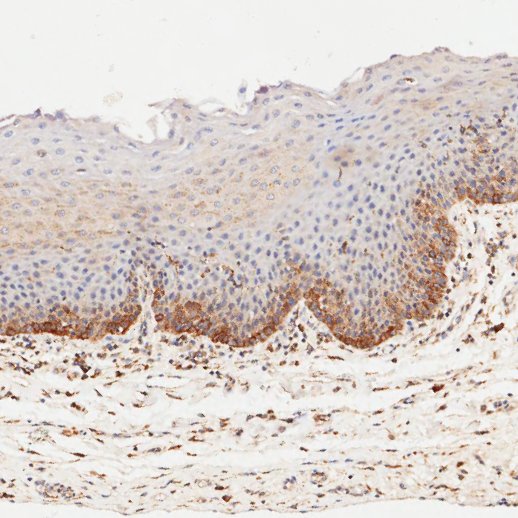

Laminin N terminus alpha31 (LaNt a31) is a really interesting laminin-related protein that the Hamill lab has been investigating for a while. Until recently, our studies focused entirely on the epithelial tissues of the skin, the surface of the eye and oral squamous cell carcinoma. However, we’ve always known that this relatively unstudied protein is also expressed by other tissues. As a first (and really important) step to understanding what this protein’s role is in tissue function, we used our new mouse monoclonal antibodies against the human form of LaNt a31 to screen a wide-range of human tissues.

Below you can see some of our favourite images from the selection. Click on an image to view as a slideshow.

You can see the whole story in the paper by Lee Troughton et al., available here.